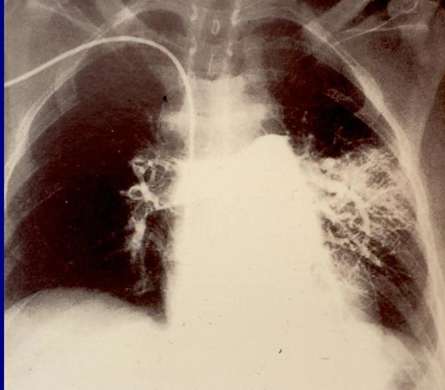

What is the diagnosis?

Saddle PE - causing a PE on both the left and right sides.